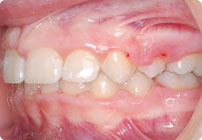

Galería

Femenino

Antes

Despues

Caso: 12 años

Adolescente: Clase II

Dental Maxilar Protrusion

Extract U4’s/L5’s

4 series de alambres:

.016″, 022″, .0215″ x .028″, .019″ x .025″ Trenzado

Elástico clase 2 2oz. TP amarillos y verdes

Retenedores: Interior Fijo de TMA y Hawley en superior

Tiempo de tratamiento: 15 Visitas